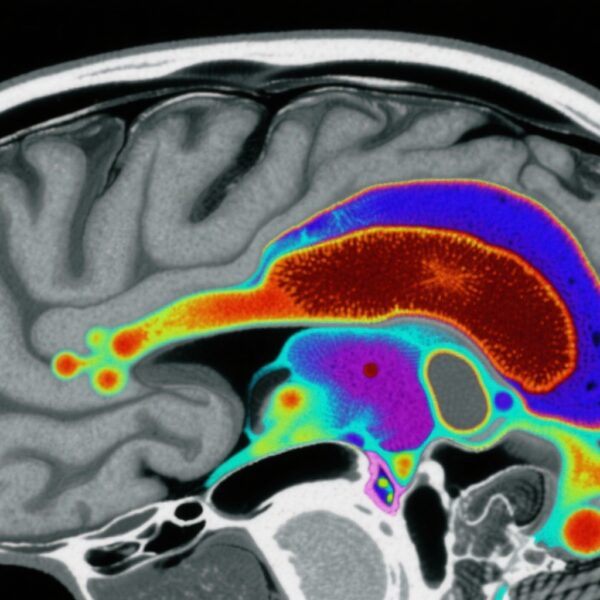

統合失調症スペクトラム障害(SSD)は、統合失調症、統合失調感情障害、一過性統合失調症を含む重度の精神障害であり、幻覚や妄想などの精神病症状が特徴です。これらの障害は、世界的に機能障害、病態、死亡率に大きな影響を与えています。米国では、SSDは約1%の生涯有病率を持つ重要な公衆衛生課題となっています。特に、疫学研究は、非ヒスパニック黒人と複数人種の人口が非ヒスパニック白人に比べてSSDの有病率が高いことを一貫して示しています。

本研究では、非高齢米国人成人(N=4,764)を対象とした全国代表的な世帯サンプルからデータを使用しました。参加者は、過去1年間および生涯のSSD(統合失調症、統合失調感情障害、一過性統合失調症)の有病率と陽性精神病症状の識別のために、DSM-5用構造化臨床面接(SCID-5)を受けました。